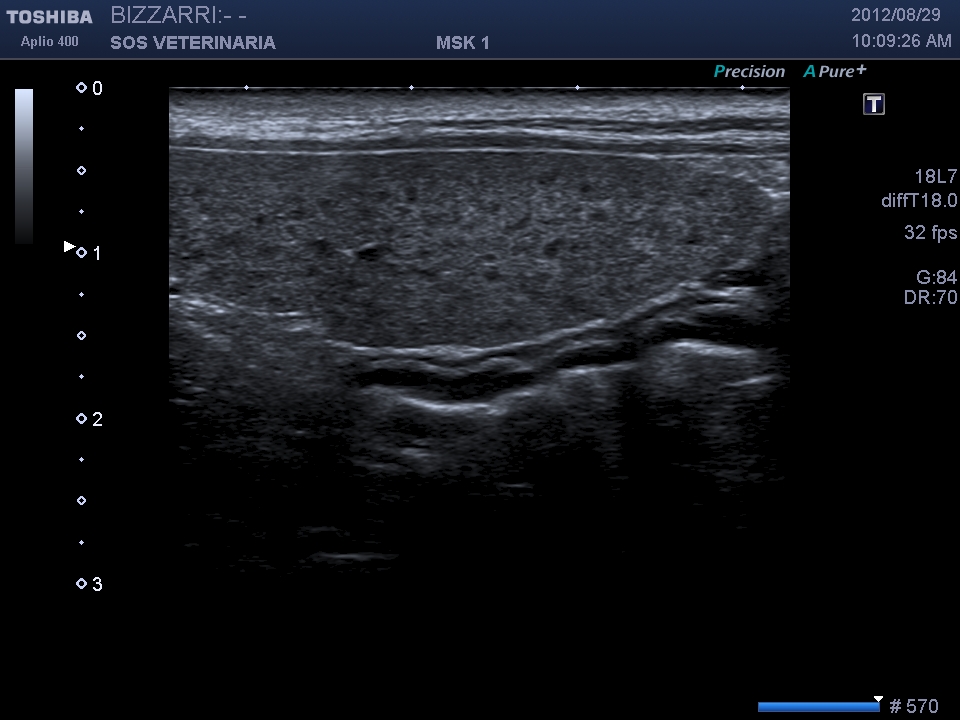

In questo caso clinico la patologia era rappresentata da una virosi con segni clinici tipici di vomito diarrea e leucopenia ,il referto dell’ascaridiosi (come spesso accade) era del tutto occasionale o al massimo un fattore complicante il decorso della malattia.